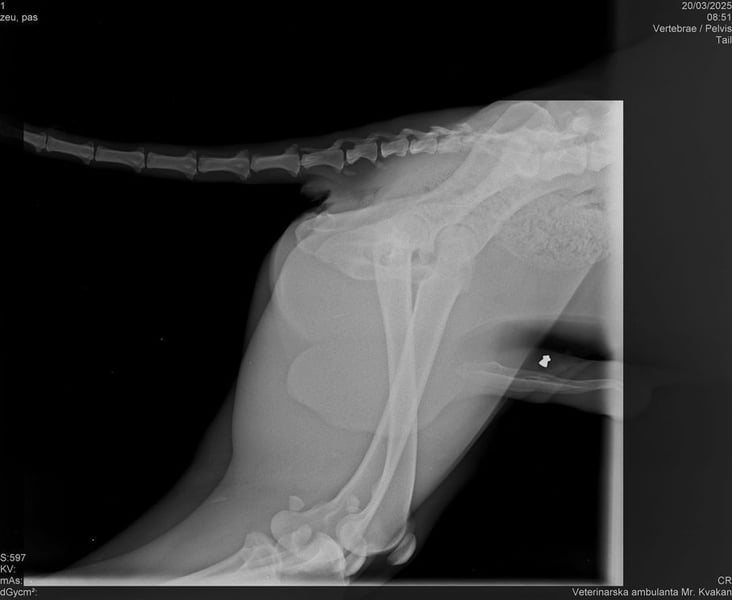

Bemerkungen: Lehmann wurde mit einer Verletzung am Hinterbeinchen gefunden. Ein Röntgenbild finden Sie in der Bildergalerie.